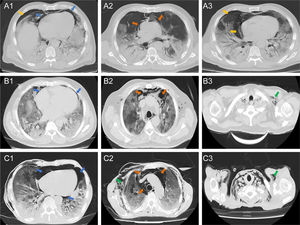

Chest CT showed that ten (83%) patients had both pneumomediastinum and pneumopericardium, while the other two patients had isolated pneumomediastinum or pneumopericardium. Out of the eleven patients with pneumopericardium, one was classified as severe. Pneumothorax was observed in five (42%) patients, four of them accompanied by pneumomediastinum. Pulmonary patterns such as ground glass opacities, crazy paving and consolidation were observed in 100%, 75% and 50% of patients, respectively. Five (42%) patients had subcutaneous emphysema and one of them had subcutaneous neck emphysema. Radiologic findings are presented in Fig. 1.

Axial tomographic sections of three patients (A, B, and C) with different degrees of gas present at the pericardial level (blue arrows), mediastinal (orange arrows), pleural (yellow arrows) and subcutaneous emphysema (green arrows). A1–3 shows a moderate presence of gas around the cardiac silhouette, large vessels, and right pneumothorax. B1 shows presence of gas in the pericardial sac (mild or laminar). C1–3 shows the severe presence of gas in the pericardium, mediastinum and subcutaneous space.